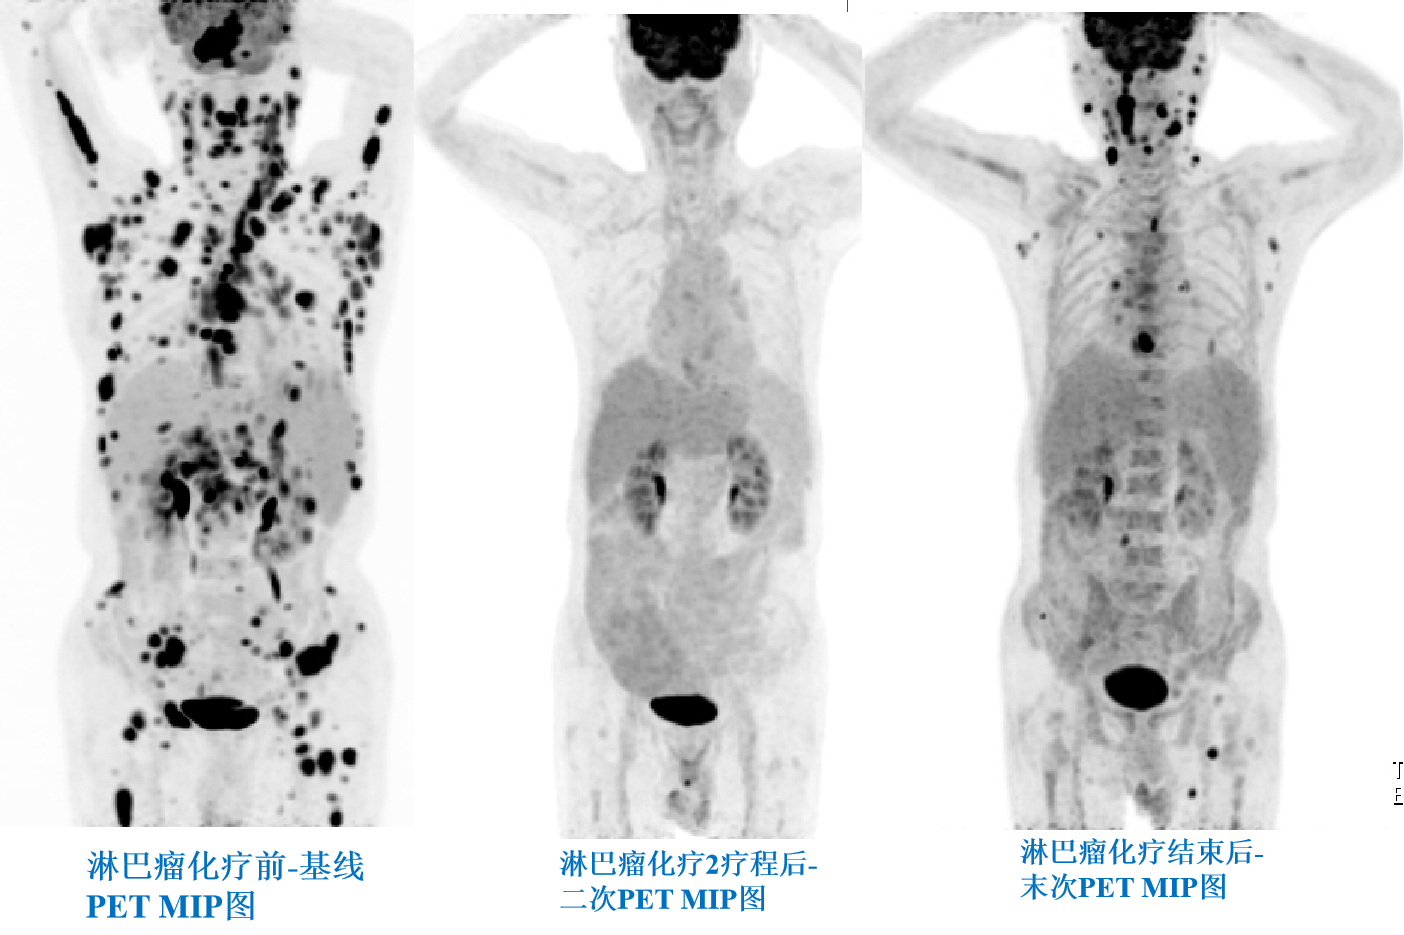

淋巴瘤化療前、中、后PETCT療效評價.png

淋巴瘤化療前、中、后PETCT療效評價